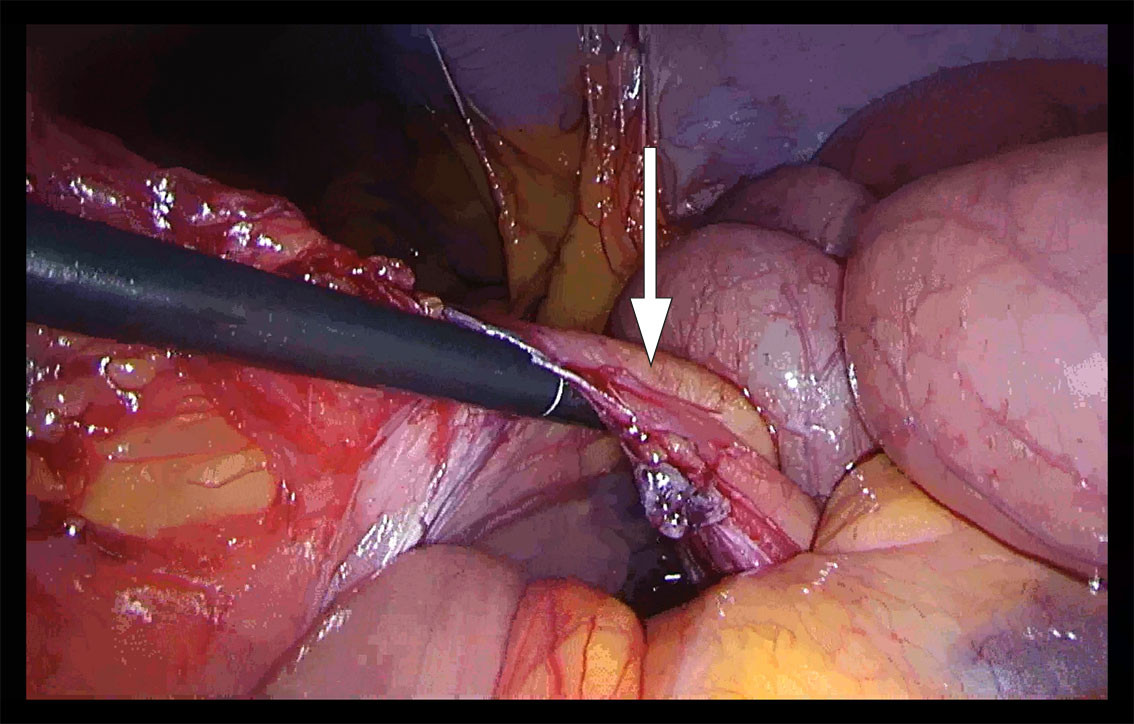

Laparoscopy was performed under general anaesthesia and found a small amount of intra-abdominal free fluid. Large areas of the small bowel were dilated. We started to reposition the small bowel to the right, firstly from proximal to distal and then in a proximal direction from the ileocaecal junction. It appeared that the small bowel was herniated under a 'cord' attached to the descending colon. On closer inspection, vascular structures could be made out, and we could not rule out the mesentery being narrow with a defect (Figure 1). Due to a large amount of dilated bowel in the surgical field, limited space and uncertainty about whether all the bowel had been repositioned, it was decided to convert to laparotomy. With a midline approach, we found mechanical small bowel obstruction from a left paraduodenal hernia with large areas of the small bowel herniated to the left, posterior to the inferior mesenteric vein. The repositioned small bowel appeared viable since there was good bowel motility and good blood circulation. Continuous sutures were placed with patent closure of the opening in the mesentery, without injuring the vascular structures.

On review of the patient's CT images, it could be seen that the inferior mesenteric vein runs anterior to the herniated small bowel loops. This was also seen intraoperatively and was consistent with the diagnosis of paraduodenal hernia (Figure 2).

The treatment of paraduodenal hernia is surgery, either by laparoscopy or laparotomy, with the objective of repositioning the small bowel and closing the opening in the mesentery (1). There are no clear guidelines for the surgical approach and how to avoid injury to the large mesenteric vessels. In paraduodenal hernia, care should be taken of the mesenteric vessels running to the anterior and medial side of the hernia, but division of these structures does not compromise blood supply to the bowel (6).